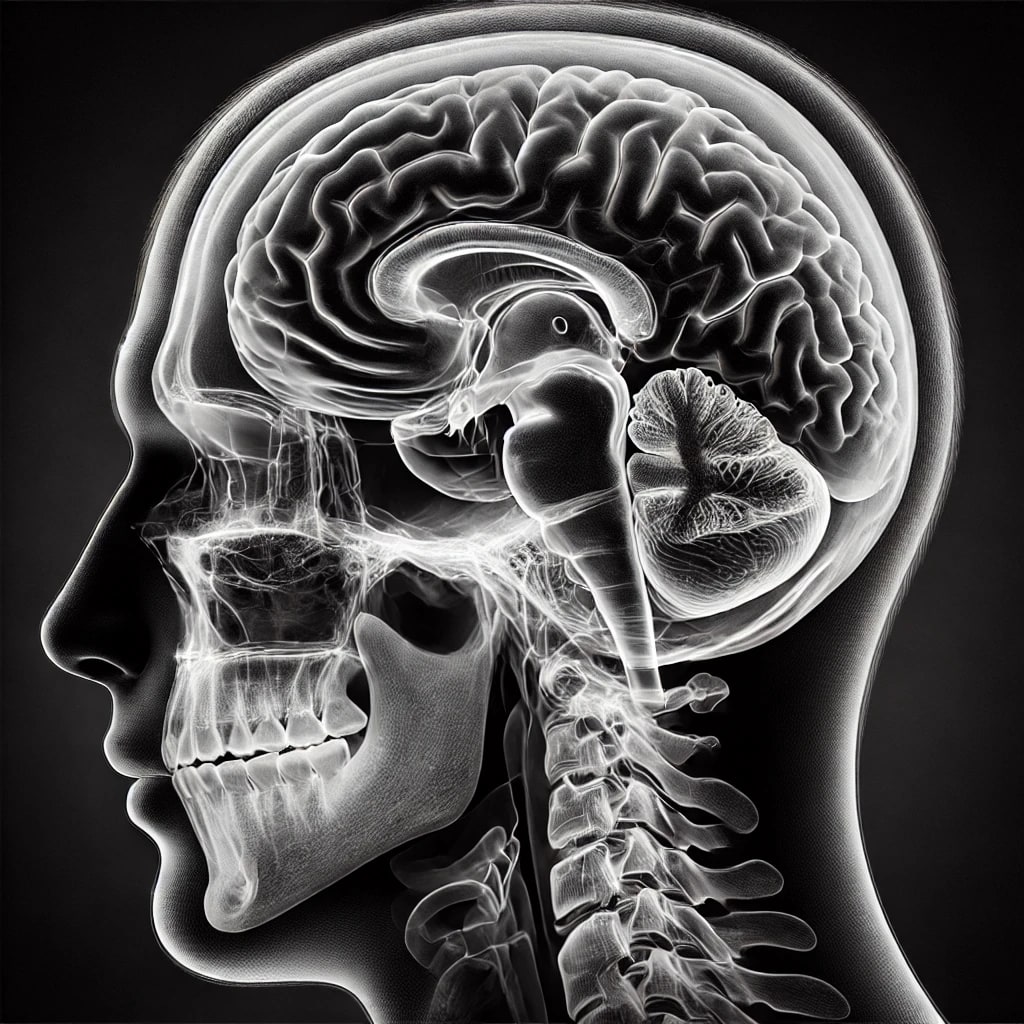

Pro zobrazení dat na webu jsme vybrali JavaScriptovou knihovnu Cornerstone3D, která umožňuje DICOM soubory nejen zobrazovat, ale můžeme u nich například měnit jas, kontrast nebo použít pravítko pro měření vzdáleností mezi zobrazenými částmi pacientova těla.